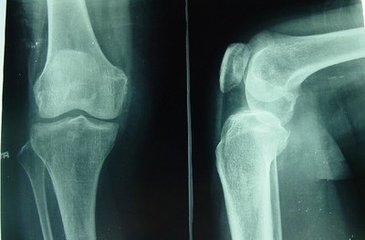

风湿性关节炎是一种常见的急性或慢性结缔组织炎症。其典型表现是 ...